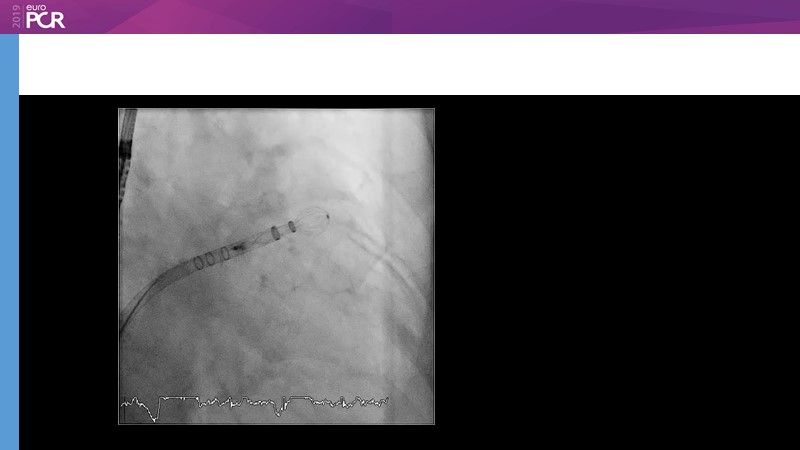

LAA closure

Left atrial appendage closure - A case-based discussion

Optimising procedural outcome and safety